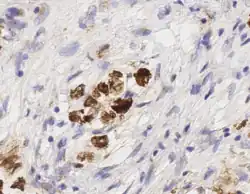

_stain_of_mixed_malignant_germ_cell_tumor_-_crop.png)

Digital pathology has been approved by the FDA for primary diagnosis.[47] The approval was based on a multi-center study of 1,992 cases in which whole-slide imaging (WSI) was shown to be non-inferior to microscopy across a wide range of surgical pathology specimens, sample types and stains.[48] As of mid 2025, approximately 50 digital pathology AIs have been cleared for primary diagnostic use (CE-IVD / CE-IVDR) in the EU.[49] While there are advantages to WSI when creating digital data from glass slides, when it comes to real-time telepathology applications, WSI is not a strong choice for discussion and collaboration between multiple remote pathologists.[50] Furthermore, unlike digital radiology where the elimination of film made return on investment (ROI) clear, the ROI on digital pathology equipment is less obvious. The strongest ROI justification includes improved quality of healthcare, increased efficiency for pathologists, and reduced costs in handling glass slides.[51]